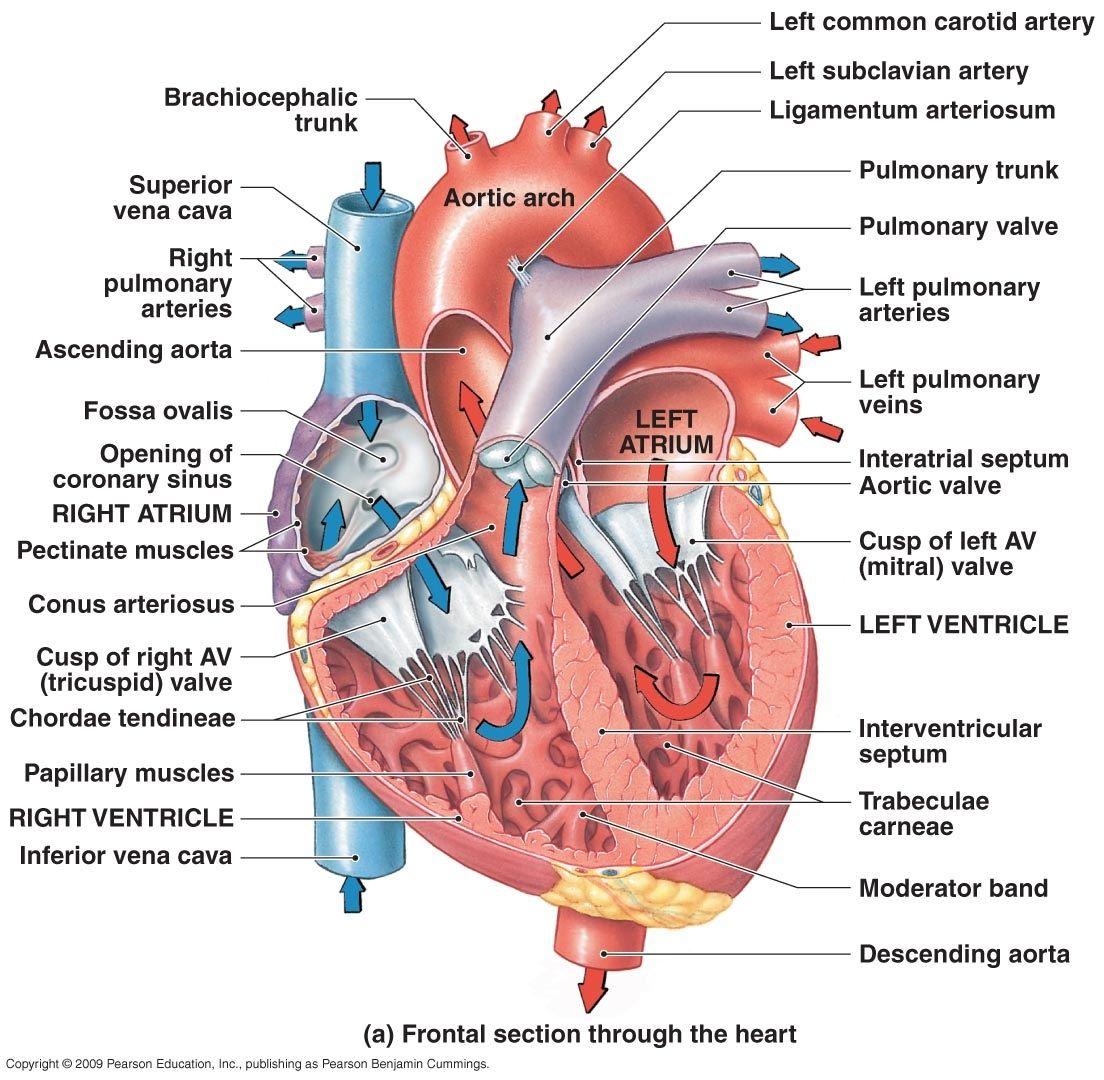

3d anatomy human heart  Show me a diagram of the human heart? Here are a bunch! - Interactive Biology, with Leslie Samuel

How the Human Heart Works | Safety and Health Solutions  3d human heart